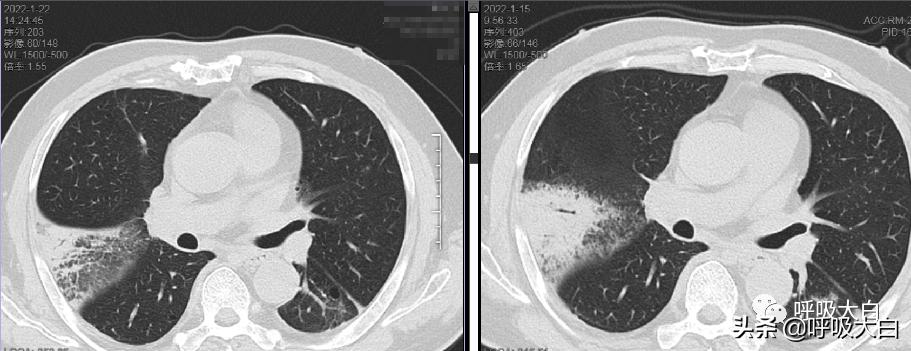

肺部影像学表现为不同程度渗出、实变,为胸膜下淡薄阴影,密度不均,病变呈扇形,肺部炎性浸润伴间质性炎症,单侧下肺叶节段实变多见,双侧实变、多发结节样或粟粒样浸润在部分患者可见,胸腔积液及肺门淋巴结病少见。

3-其他病例胸部CT

治疗后 治疗前